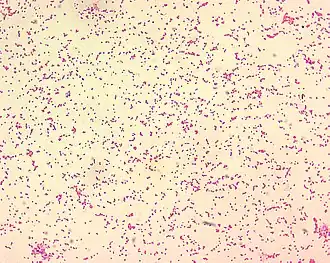

La morfología de tinción de Brucella spp. es gramnegativa. Brucella spp. son cocobacilos gramnegativos pequeños (0,5-0,7 x 0,6-1,5 µm) que se tiñen mal y se observan principalmente como células individuales con aspecto de "arena fina". | ||